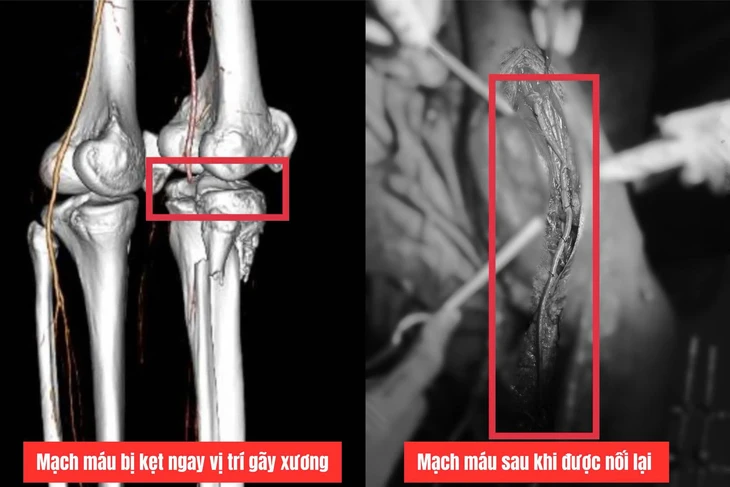

Kết quả chụp CT cho thấy bệnh nhân bị mất tín hiệu động mạch khoeo và chày trước, tiên lượng nguy cơ cắt cụt chân phải do thiếu máu chi kéo dài.

Bác sĩ phát hiện động mạch bị kẹt giữa ổ gãy xương, đoạn động mạch khoeo và chày trước dập, tắc dài gần 20cm.

Ê kíp quyết định thực hiện phẫu thuật "bắc cầu động mạch khoeo", lấy đoạn tĩnh mạch chân trái dài khoảng 40cm để nối thay thế đoạn động mạch khoeo bị tổn thương, tái lập dòng chảy từ đùi xuống cẳng chân.

Đoạn động mạch bị tổn thương được thay thế bằng tĩnh mạch từ chân còn lại - Ảnh: Bệnh viện Đa khoa Quảng Trị